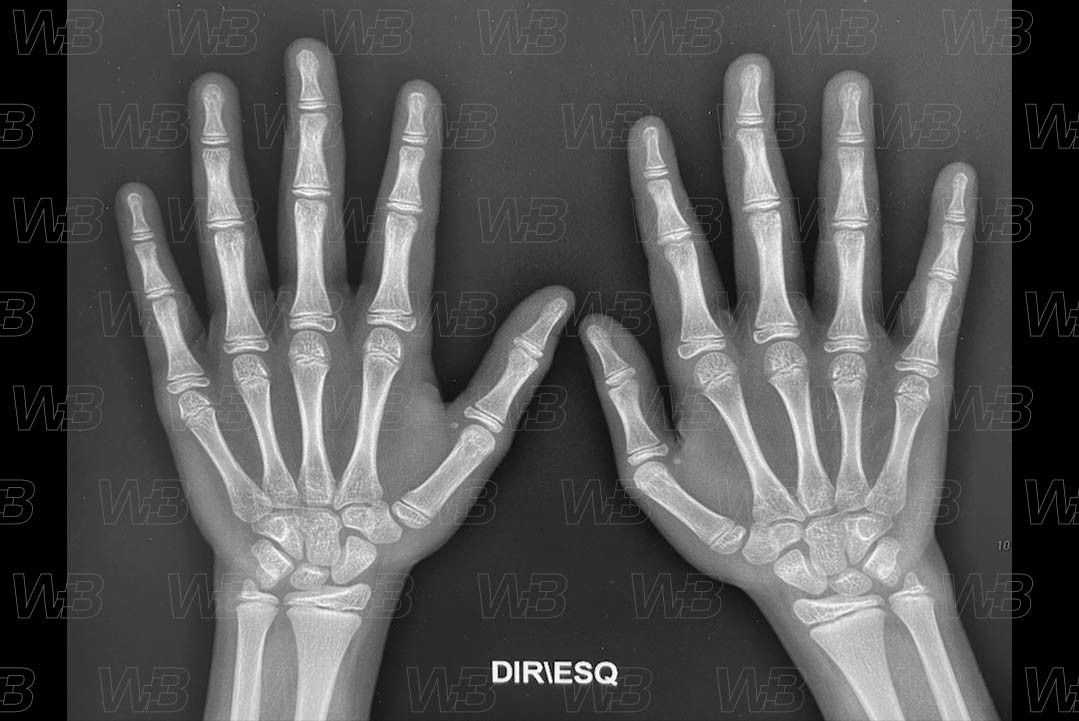

RADIOGRAFIA MÃOS E PUNHOS (IDADE ÓSSEA) [cms-watermark]

Feminino

11 anos:

• Sesamoide adutor e flexor do polegar;

• Epífises do segundo ao quinto metacarpos são tão largas quanto as metáfises;

• Epífises das falanges médias e proximais do segundo ao quinto dedo e das falanges distais de todos os dedos capeiam as metáfises.